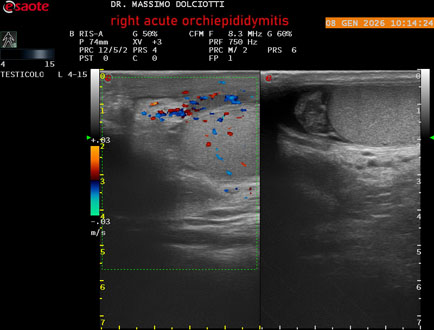

Data inserimento: 08/01/2026

Ecografia del: 08/01/2026

Strumento: Esaote MyLab Eight

Sonda: Lineare Multifrequenza 4-15 MHz

Età Paziente: M 74 anni

Motivazione dell'esame: da 3 giorni dolore e tumefazione al testicolo destro.

Commento all'esame: le immagini ed il video documentano il didimo destro, aumentato di volume, con incremento della vascolarizzazione; aumentato di volume e di vascolarizzazione anche l'epididimo destro, Normale il didimo sin e l'epididimo sinistro, Gli elementi ecografici segnalati orientano per orchiepididimite destra acuta.

Conclusioni: orchiepididimite destra acuta (right acute orchiepididymitis).

Presentazione: Dr. Massimo Dolciotti - Ancona